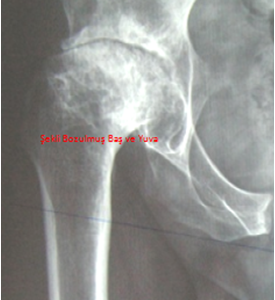

KALÇA KİREÇLENMESİ

KALÇA KİREÇLENMESİ(Os...